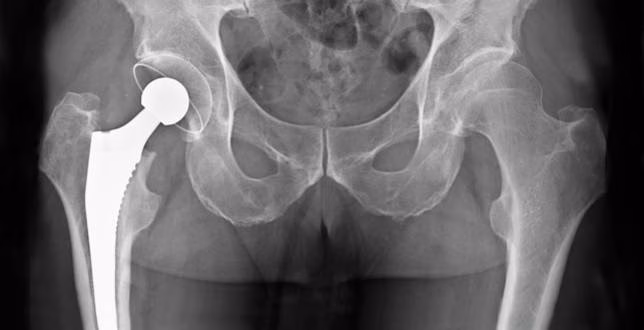

Por poner un ejemplo, la prótesis de cadera o artroplastia consiste en la sustitución total o parcial de la cadera por una articulación artificial. En España se realizan unas 30.000 operaciones de este tipo al año.

También es importante que se practique fisioterapia respiratoria para evitar complicaciones respiratorias. La visita del fisioterapeuta comienza el mismo día de la operación o al día siguiente. En esta etapa es importante que el fisioterapeuta explique al paciente consejos generales durante las primeras semanas para evitar problemas posteriores como puede ser la luxación de la prótesis, obligando al paciente a regresar al quirófano y retrasando más la recuperación. Entre las recomendaciones relativas a una prótesis de cadera hay las siguientes:

No cruzar las piernas; Colocar una almohada entre las piernas para evitar el cruce de piernas mientras se duerme o rotaciones en la cadera; No inclinarse mucho hacia delante cuando se encuentre sentado; No acostarse sobre el lado sano, en los primeros momentos tampoco se debe hacerlo sobre el lado operado. Se comenzará "boca arriba" hasta que el médico aconseje otra postura; No efectuar rotaciones con las piernas, sobretodo atención a la rotación interna; No sentarse en sillas demasiado bajas, buscar alguna solución en caso de que la cama también lo sea; No viajar en coche si no es necesario las primeras 6 semanas.